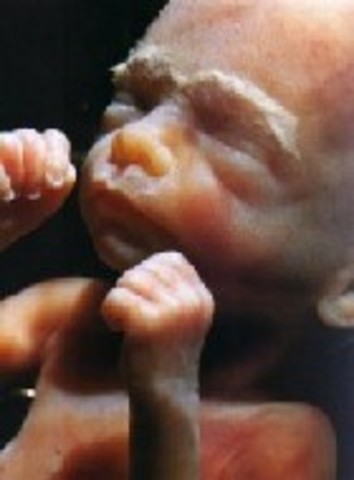

• Week Nine Developments

Week Nine Developments

The embryo's limbs are beginning to lose their tadpole-like look and start to form hands, feet, and touch pads. Organs and nerves are beginning to function.